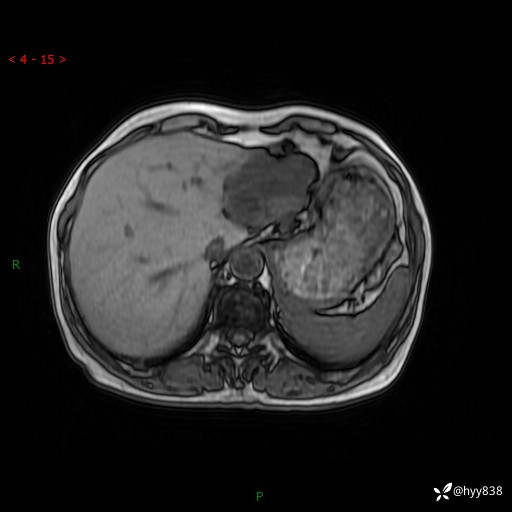

肝脏MRI平扫(同反相位)

增强(动脉期+静脉期+延迟期)